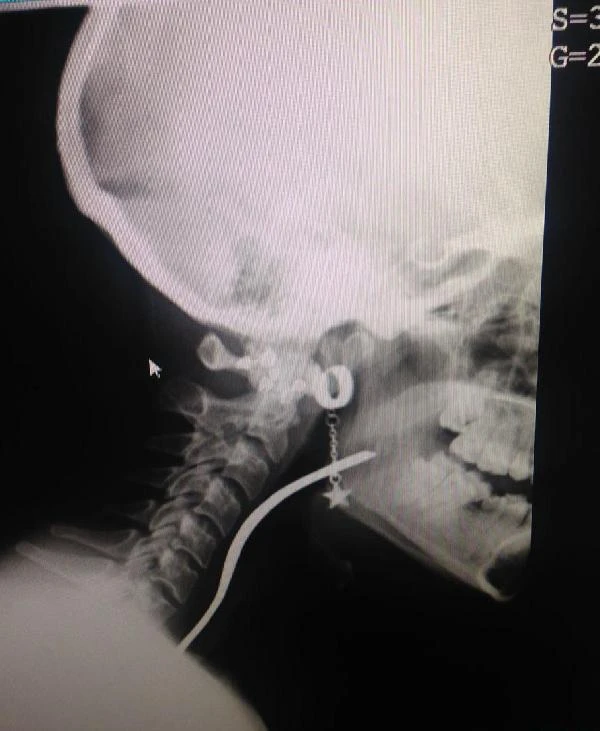

Uludağ Üniversitesi Tıp Fakültesi Hastanesi’ne kaldırılan Naciye Ak’ın boğazına kaçan çatal operasyonla çıkarılırken, genç kızın sağlık durumunun iyi olduğu bildirildi. Olay, dün gece saat 22.30 sıralarında Orhangazi’ye bağlı Üreğil Mahallesi’nde meydana geldi. İddia göre, iftardan sonra çürüyen dişinin arasına giren yiyecek parçalarını çıkarmak isteyen Naciye Ak, çatalla dişini karıştırmaya başladı. Çatal, genç kızın elinden kayarak boğazına girdi. Naciye Ak ailesinden yardım isteyince taksic baba İsmail Hakkı Ak, kızını kendi aracıyla Orhangazi Devlet Hastanesi’ne kaldırdı. Buradaki ilk müdahalenin ardından Uludağ Üniversitesi Tıp Fakültesi Hastanesi’ne kaldırılan genç kızın boğazındaki çatal operasyonla çıkarıldı.

Sağlık durumu iyi olan kızının bugün akşam saatlerinde taburcu edilmesini beklediklerini söyleyen İsmail Hakkı Ak, “İftardan sonra durakta beklerken eşim arayarak, ‘Koş Naciye ölüyor’ diyerek durumu haber verdi. Eve gelip hastaneye götürdüm. Naciye’nin dişlerinden bazıları çürüğü için sürekli şikayet ediyordu. Dişlerini karıştırdığı çatal boğazına kaçmış. Bir türlü doktora götürememiştik” diye konuştu.